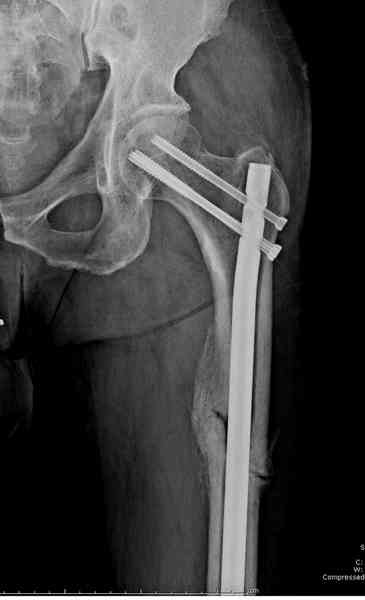

На второй день (7) обнаружен пропущенный перелом,

и проведены шурурпы через и спереди штифта без удаления.

Послеоперационные снимки